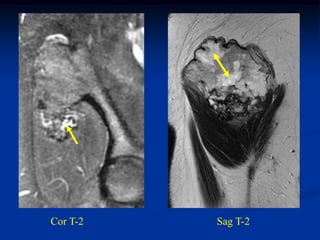

CLASSIC Case #123

12 year female with chondroblastoma proximal tibia

Coronal post gad MRI

Sagittal T-2 MRI

Photomic